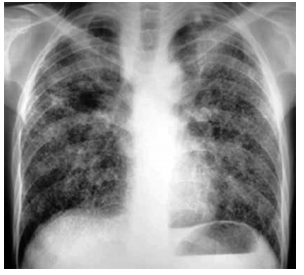

Paciente do sexo masculino, 42 anos, proveniente do Ceará, procura atendimento médico por dispneia de longa data, mais intensa nos últimos 3 meses. Refere que há 22 anos trabalha escavando poços de água potável. Seu estado geral é bom, não há queixa de febre ou de outros sintomas associados.

Analise a radiografia de tórax, ilustrada a seguir, e assinale a alternativa que contém a hipótese diagnóstica correta para o caso relatado.